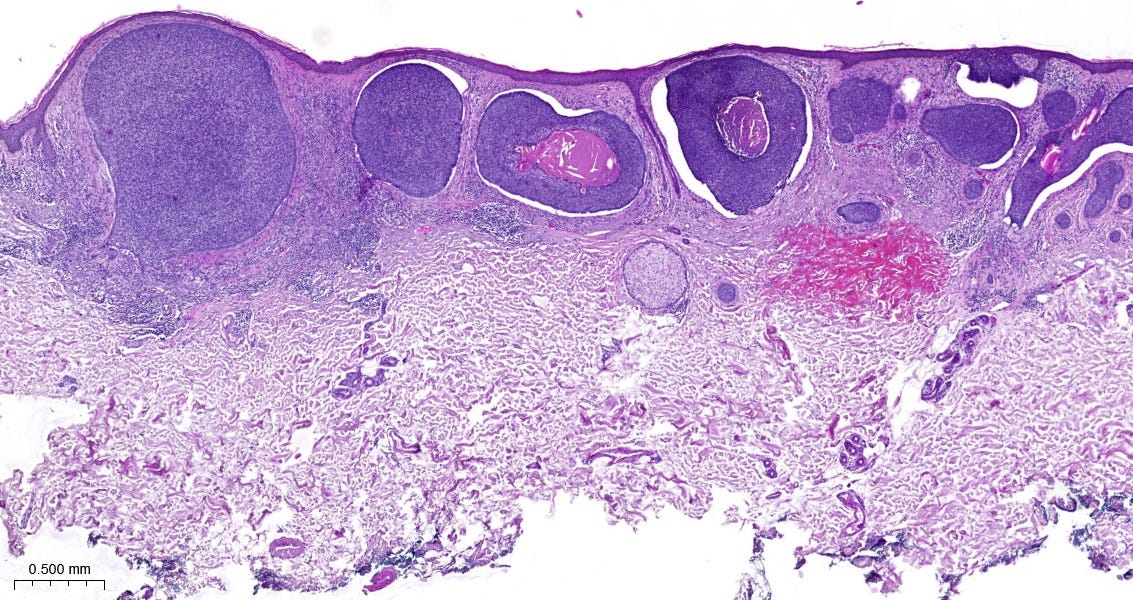

Histopatologický kvíz

📝 V dnešnom kvíze budeme cestovať v čase do 3. ročníka medicíny, na skúšku z patológie na konci letného semestra (úroveň 1/5). Toto „sklíčko” sa na skúške určite objaví, dobre si ho zapamätaj! 🤓 Odpoveď nájdeš na konci príspevku.

Riešenie histopatologického kvízu

✅ B. Bazocelulárny karcinóm (bazalióm).

💡 Ide o najčastejšie sa vyskytujúci malígny nádor kože, ktorý postihuje najmä staršiu vekovú populáciu. Podľa rizika rekurencie zaraďujeme histologické subtypy bazaliómov do skupiny s nízkym alebo vysokým rizikom. Bazaliómy sú malignity, ktoré zriedkavo tvoria metastázy.

O diagnóze si môžeš prečítať viac na PathologyOutlines. 😉